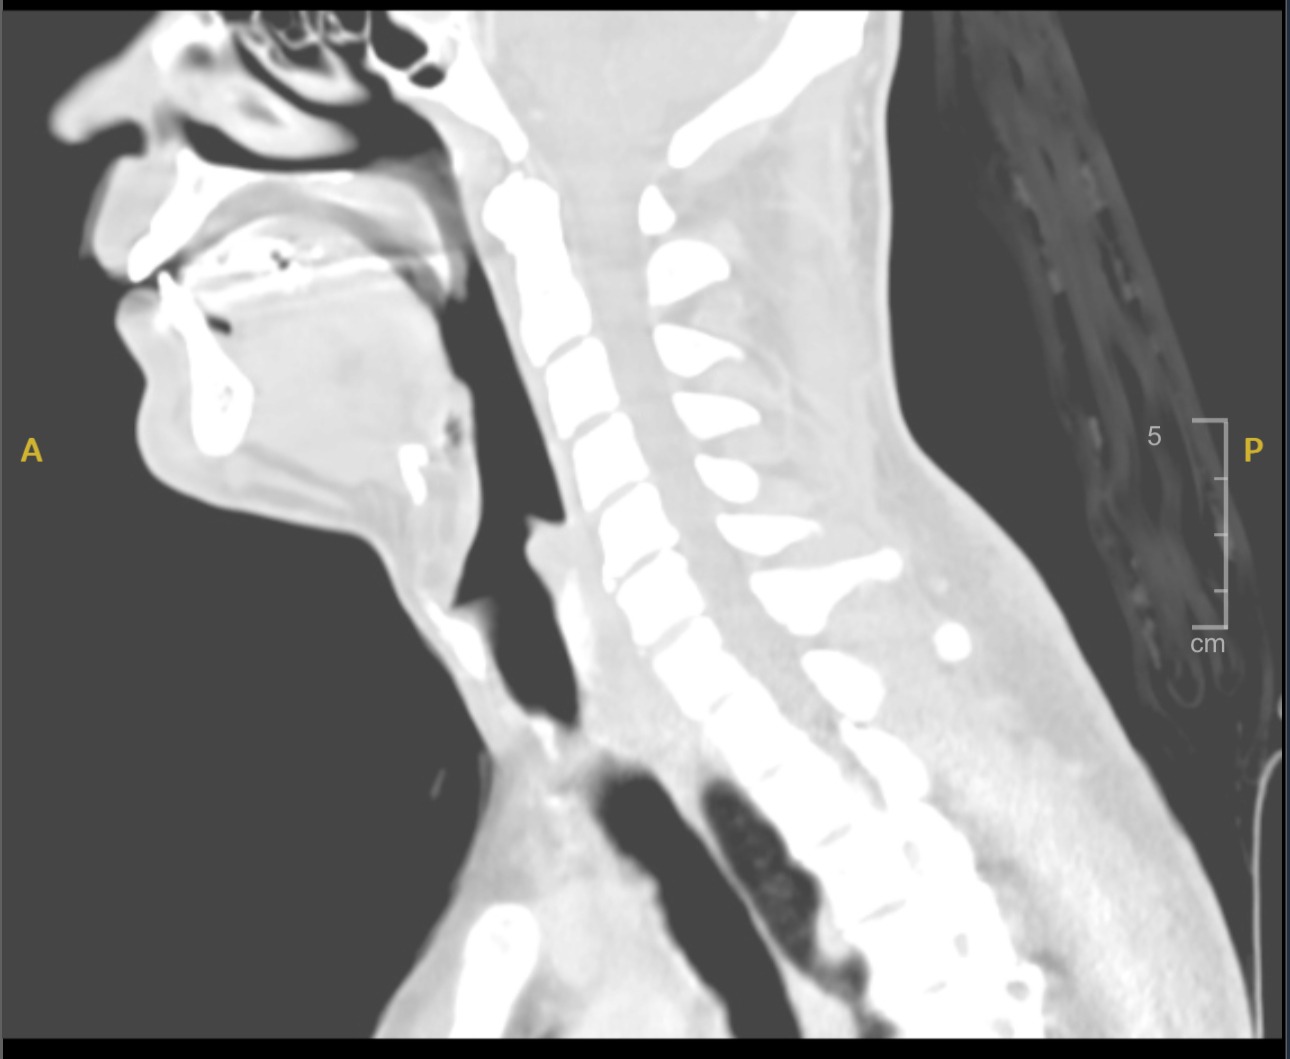

I assumed I was never going to have the same lung capacity that I had before, and that this was “my new normal”, but apparently my lungs had fully healed and the problem wasn’t a diminished lung capacity. I had scar tissue and a growth in my trachea. It seems that while I was intubated in Brazil, this caused what is known as a Tracheal Stenosis. This narrowing occurred slowly over time. Over the winter I had several chest infections, which made it worse, because of the narrowing, it also made it difficult to get infections (phlegm) out of my lungs. After months, my doctors finally decided it was best to do a tracheal resection surgery. Below are photos from my MRI/CT images and my endoscopy images.

That’s why on Tuesday April 29th I underwent a surgery to remove this Stenosis, known as a Tracheal Resection. It’s a complex surgery in a very sensitive area of the body (in my neck) where all of the major nerves and arteries exist in close proximity. During my consultation with the doctor, he indicated that this surgery will be more complex than initially anticipated considering I have 5-6cm of tissue in my trachea that must be removed, whereas typically people remove only 2-3cm of tissue. This significantly increased the likelihood complications during the surgery. The list of post-surgery complications is long as well; feeding tube, infections, severe nerve damage and other serious effects are very possible.